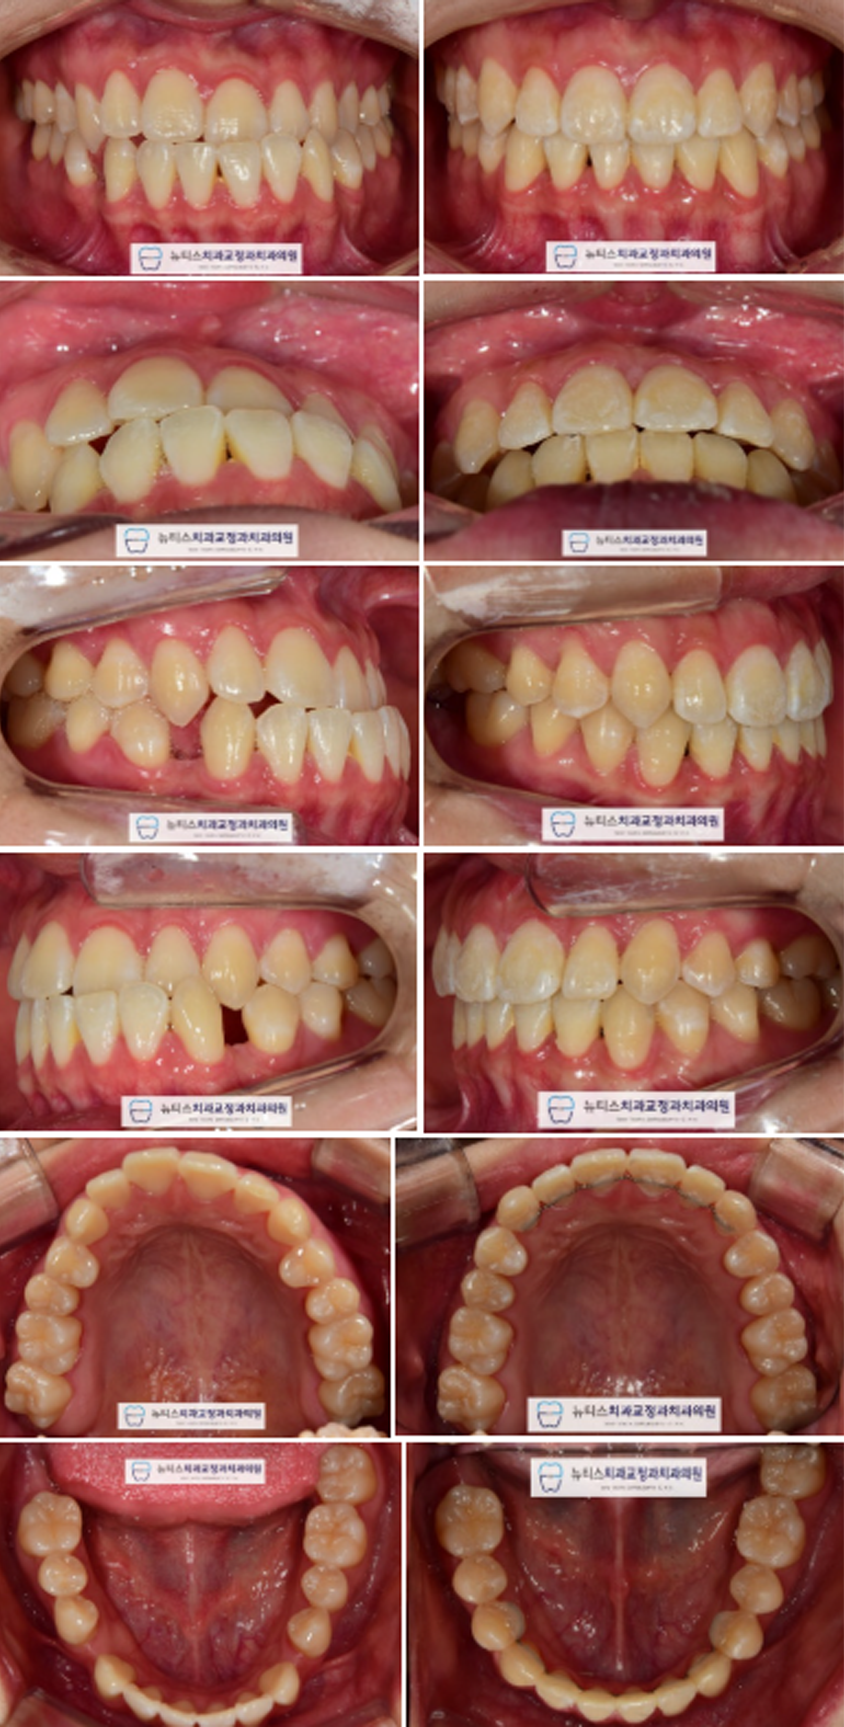

ÃÊÁø »çÁøÀÔ´Ï´Ù.

¾Æ·¡ ¾Õ´Ï°¡ À§¿¡ ¾Õ´Ïº¸´Ù ¾ÕÀ¸·Î ³ª¿ÍÀÖ´Â

#¹Ý´ë±³ÇÕ ÀÔ´Ï´Ù.

¶ÇÇÑ ÇϾǿ¡´Â ¹ßÄ¡µÈ Ä¡¾Æ°¡ ¾ø´Âµ¥µµ

»ó´çÇÑ Å©±âÀÇ °ø°£À» º¸ÀÔ´Ï´Ù.